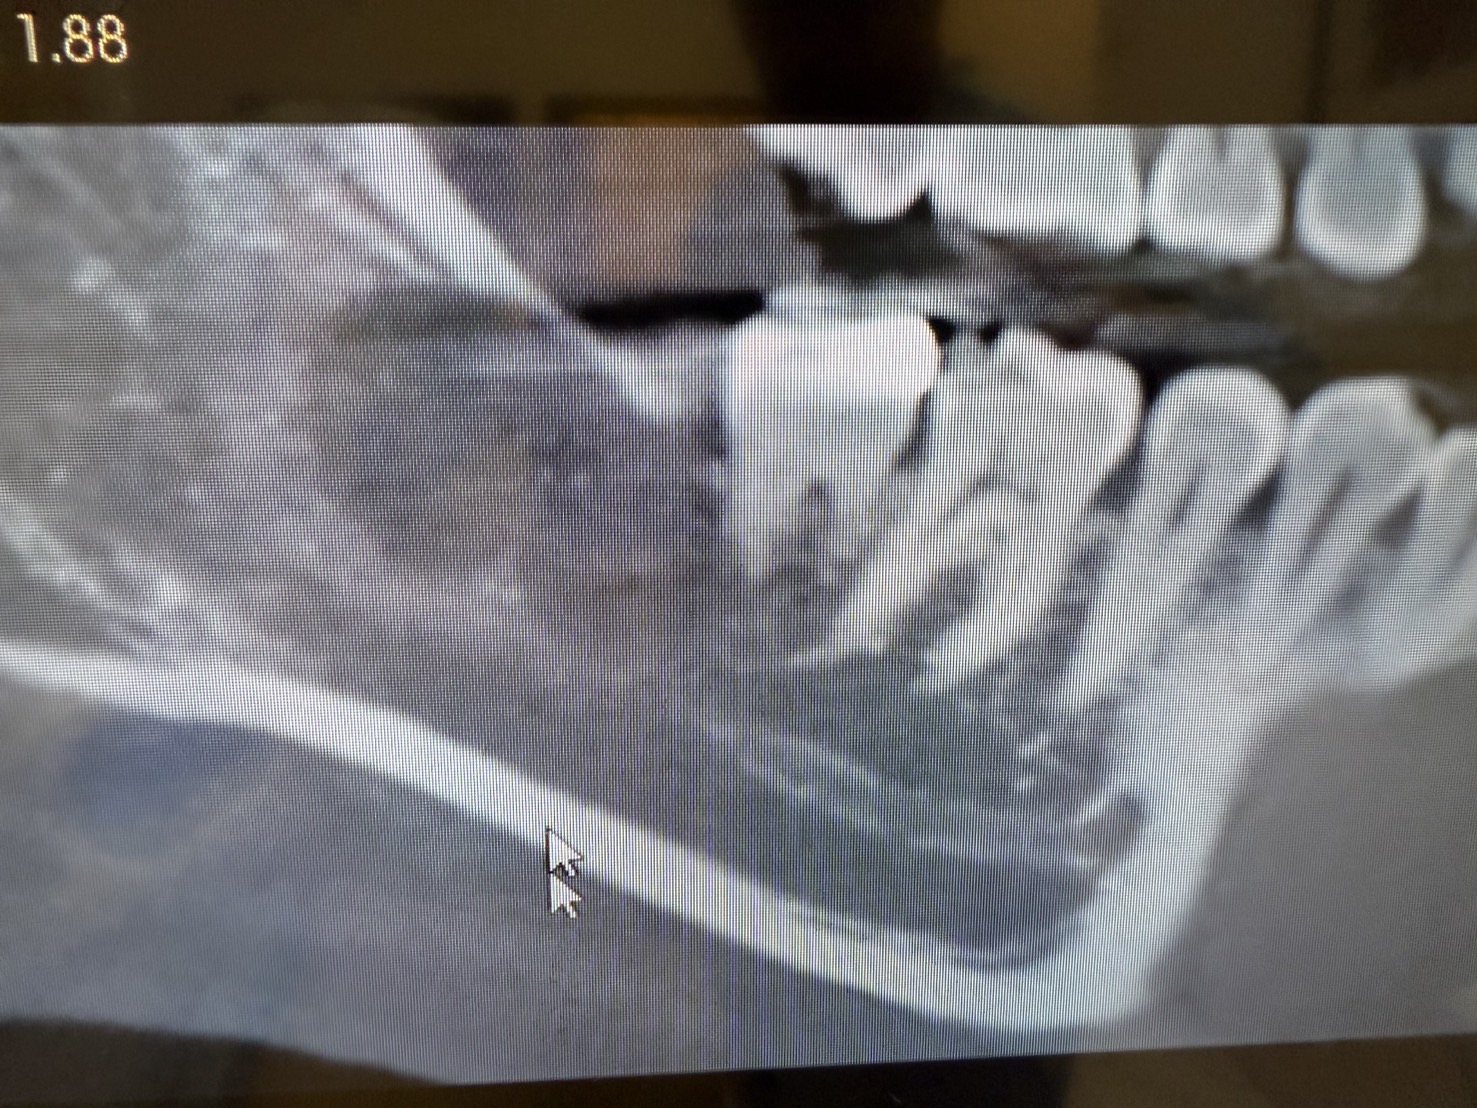

この患者さまは、親知らずに痛みがあり来院されました。こちらがCT撮影をした結果です。親知らずの横の下顎の骨の中に大きな膿の袋、嚢胞が形成されています。

X線、CTスキャン撮影の画像診断で嚢胞の正確な位置や大きさを特定し、嚢胞が周囲の骨や歯に与える影響を確認します。また歯の治療歴や外傷、や副鼻腔炎の治療歴なども詳細に確認します。そのうえで、治療計画をたてていきます。